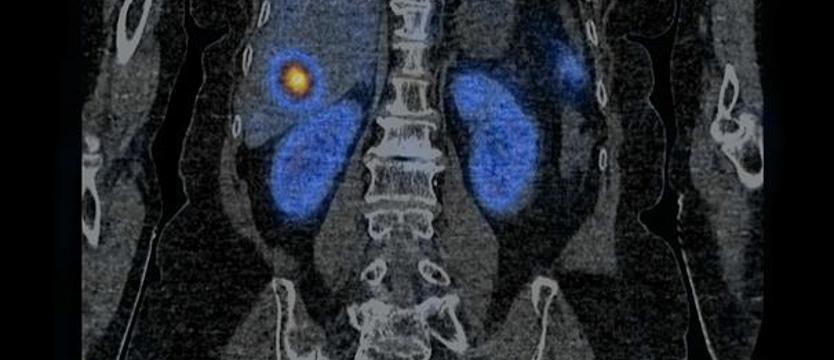

Po raz pierwszy w województwie zachodniopomorskim zastosowano terapię radioizotopową z wykorzystaniem radiofarmaceutyku 177Lu Lutathera u pacjentki z rozpoznaniem atypowego rakowiaka płuc z obecnością przerzutów. Zrobiono to 11 maja w Zakładzie Medycyny Nuklearnej w Samodzielnym Publicznym Szpitalu Klinicznym nr 1 w Szczecinie. To nowoczesna forma leczenia guzów neuroendokrynnych i od kilku miesięcy terapia ta jest objęta refundacją w ramach programu lekowego.

177Lu Lutathera łączy się z receptorami znajdującymi się na powierzchni komórek nowotworowych. Ponadto radiofarmaceutyk ten zawiera radioaktywne izotopy, które emitują promieniowanie jonizujące. Promieniowanie uszkadza DNA komórek nowotworowych, powodując niszczenie lub zahamowanie ich zdolności do podziału i wzrostu. Podobne działanie promieniowania jonizującego stosuje się w radioterapii. Dzięki selektywnemu łączeniu się z komórkami nowoworowymi, radiofarmaceutyki terapeutyczne są w stanie skutecznie zwalczać komórki nowotworowe, a emitowane promieniowanie, z uwagi na bardzo krótki zasięg, nie powoduje znaczącego uszkodzenia zdrowych tkanek.

– W Zakładzie Medycyny Nuklearnej w Szczecinie leczenie 177Lu Lutathera zostało zaprojektowane z myślą o spersonalizowanym podejściu do każdego pacjenta – informuje dr Joanna Woźnicka, rzeczniczka szpitala klinicznego nr 1 w Szczecinie. – Przed i po leczeniu przeprowadza się badania obrazowe, które umożliwiają ocenę tempa metabolizmu znacznika, które różni się u poszczególnych pacjentów. Pozwala to na dostosowanie terapii do indywidualnych potrzeb i zwiększa szansę na osiągnięcie pozytywnych rezultatów terapeutycznych. Ta innowacyjna forma terapii, łącząca działanie molekularne i promieniowanie jonizujące, otwiera nowe perspektywy w zwalczaniu nowotworów. Dzięki ciągłemu rozwojowi nauki i technologii coraz więcej pacjentów może skorzystać ze skutecznych i bezpiecznych metod terapeutycznych, które mają na celu zahamowanie wzrostu komórek nowotworowych i poprawę jakości życia pacjenta.